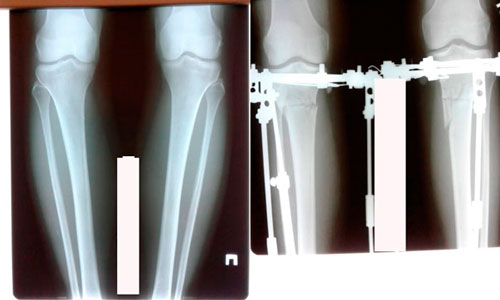

Исходник - 42 года.

Дата операции - 04.06.2020

до круток